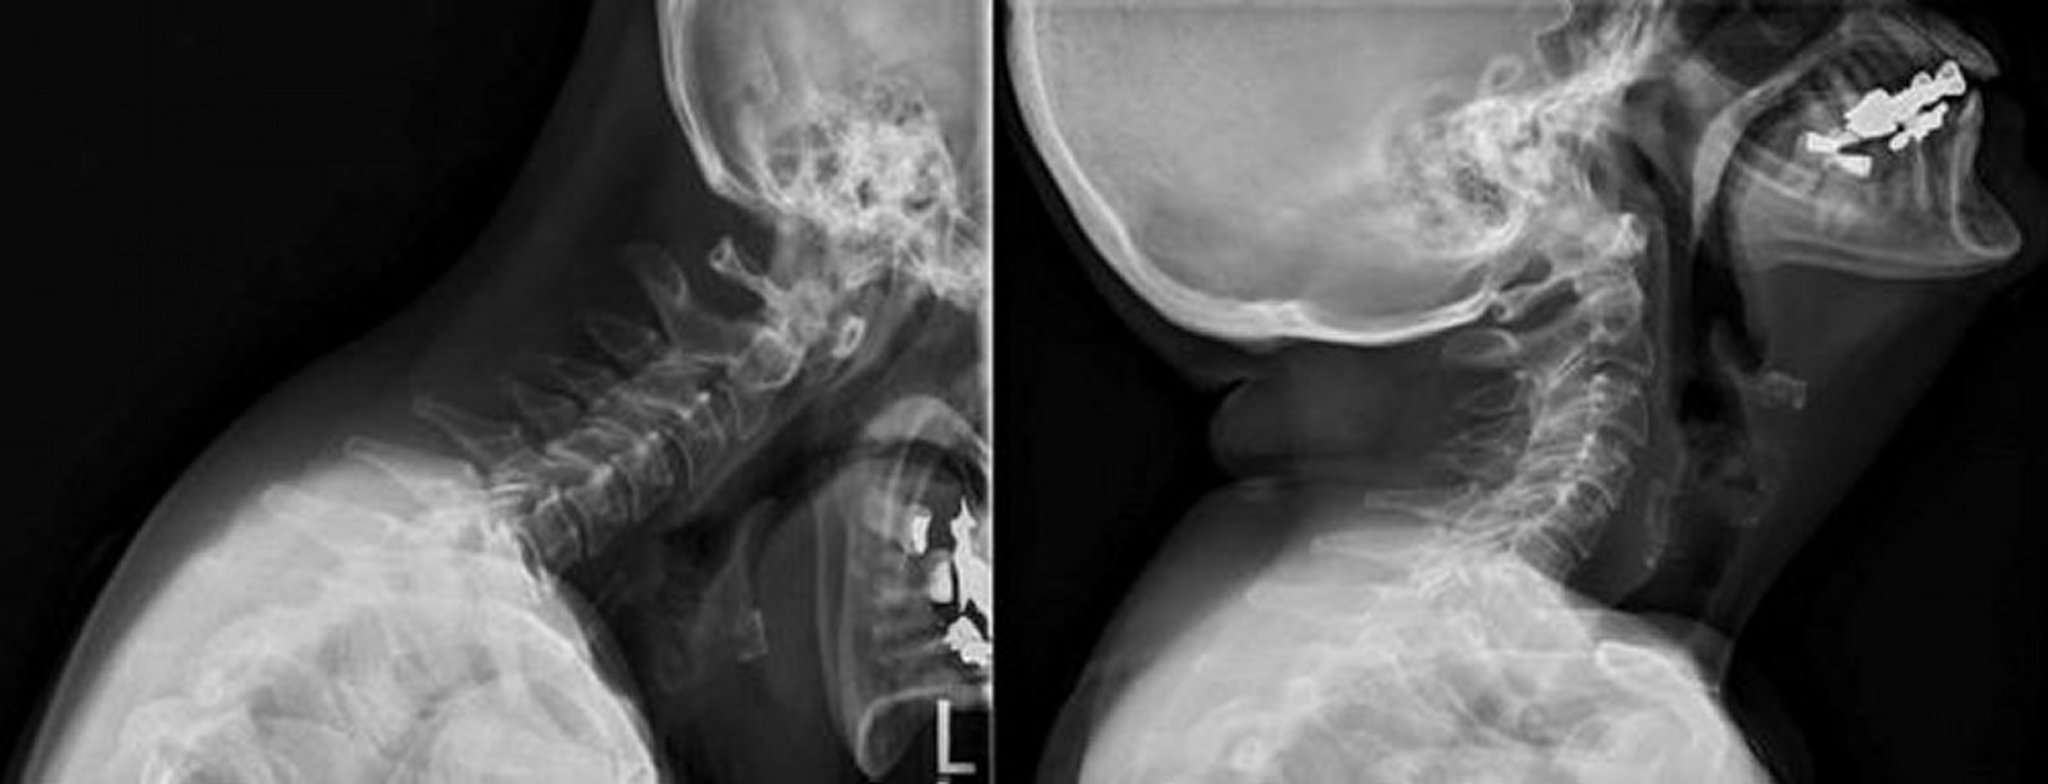

Cervical Spine Involvement in Rheumatoid Arthritis

These flexion and extension radiographs of the cervical spine show widening of the atlantoaxial distance measuring up to 5 mm on the flexion view, which reduces with extension.

Image courtesy of Kinanah Yaseen, MD.